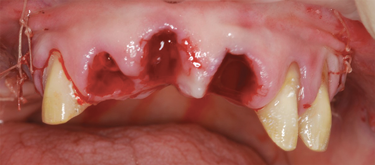

Bilateral maxillary sinus grafts were performed. The provisional restorations were removed from teeth Nos. 6, 10, and 11, and the preparations were cleaned of all residual cement. The maxillary teeth were extracted, leaving teeth Nos. 6, 10, and 11 in place (Figure 17). The extraction sockets were fully debrided and thoroughly irrigated.

Fig 17. After completion of sinus grafting, the individual provisional restorations were removed and all maxillary teeth that were not to be used to support the provisional restoration were extracted.